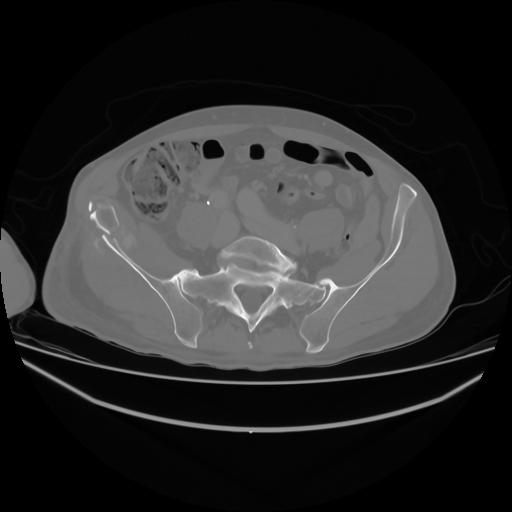

4 CUERPO,CE,Axial,3.0,CUERPO,,